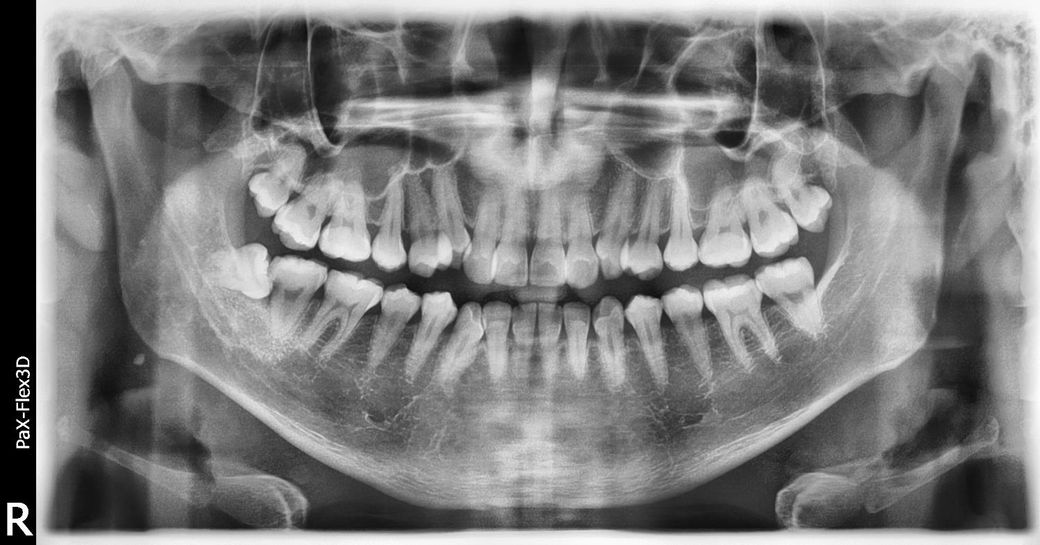

사랑니 옆 어금니 충치 때문에 사랑니를 발치했는데 궁금한게 있습니다.

사진상으로 왼쪽아래 사랑니 앞치아는 충치가 많이 진행된거 같습니다. 신경치료를 하거나 심하면 발치를 해야될정도 안좋은곳에충치가 생긴거 같습니다.

사진으로 봤을 경우에 사병니 앞에 있는 부위의 충치는 잇몸 안쪽으로 깊게 들어간 것으로 보입니다. 간단하게 촉지를 치료한다기보다 크라운 등의 치료를 하는 것이 좋을 것으로 생각됩니다.

1.충치 부분만 갈아내고 때우기가 가능한거 같나요 -> 충치가 좀 깊고 잇몸 하방입니다. 사랑니가 이제 없으니 접근은 되겠으나 신경치료 가능성이나 인레이 가능성도 있습니다.